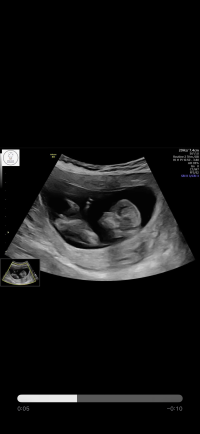

Så godt å høre at alt står bra til. Skummelt å blø. Er det vanligere med hematom etter ivf? Håper det forsvinner raskt!Ble ekstra ultralyd i dag pga brun utflod , styrt på lørdag rett igjen klær og alt , litt brunt i formiddag igjen så fikk bestilt privat ul , er 10+0, lille ble målt helt perfekt og fikk både se og høre hjertelyd.. hematomet hausken såg i uke 7 ved sist blødning er ikke borte. Men hjerte slo og alt sto bra til,hun jeg var hos sa at enten absorberes resten av hemstomet eller så vil det blø ut.. uansett like skummelt .. men godt få sjekka.. blødd en del frisk etter hun holdt på trykke på magen men dobbel sjekka med doppleren min nå i kveld og hjerte slår det.. en får bare litt heta.. håper dette er siste rest som blør ut..vi såg begge at det var mer .. ny privat ul på torsdag ..fikk både filmer og bilder .. veldig fornøyd . Kan anbefales var i Stavanger på meretes ultralyd hun stilte opp etter arbeidstid

Vis vedlegget 439593

Netopp vært på ultralyd og oppfølging på sykehuset , blir tettere oppfølging nå og jeg kan bare ringe og kome om det er noe.ikke tegn til noe mer blødning nå , sannsynligvis har det blødd ut men alikevel var de ikke helt sikker..men såg bra ut. Lille sprella og hjerte slo. Alt bare fint. Har litt veske i buken og cyster etter ivf stimulering som de også vil følge ekstra opp.. veldig flink og hyggelig lege . Og veldig gla alt sto så bra til.og at helsevesenet funker så blir ekstra ultralyder dær også.